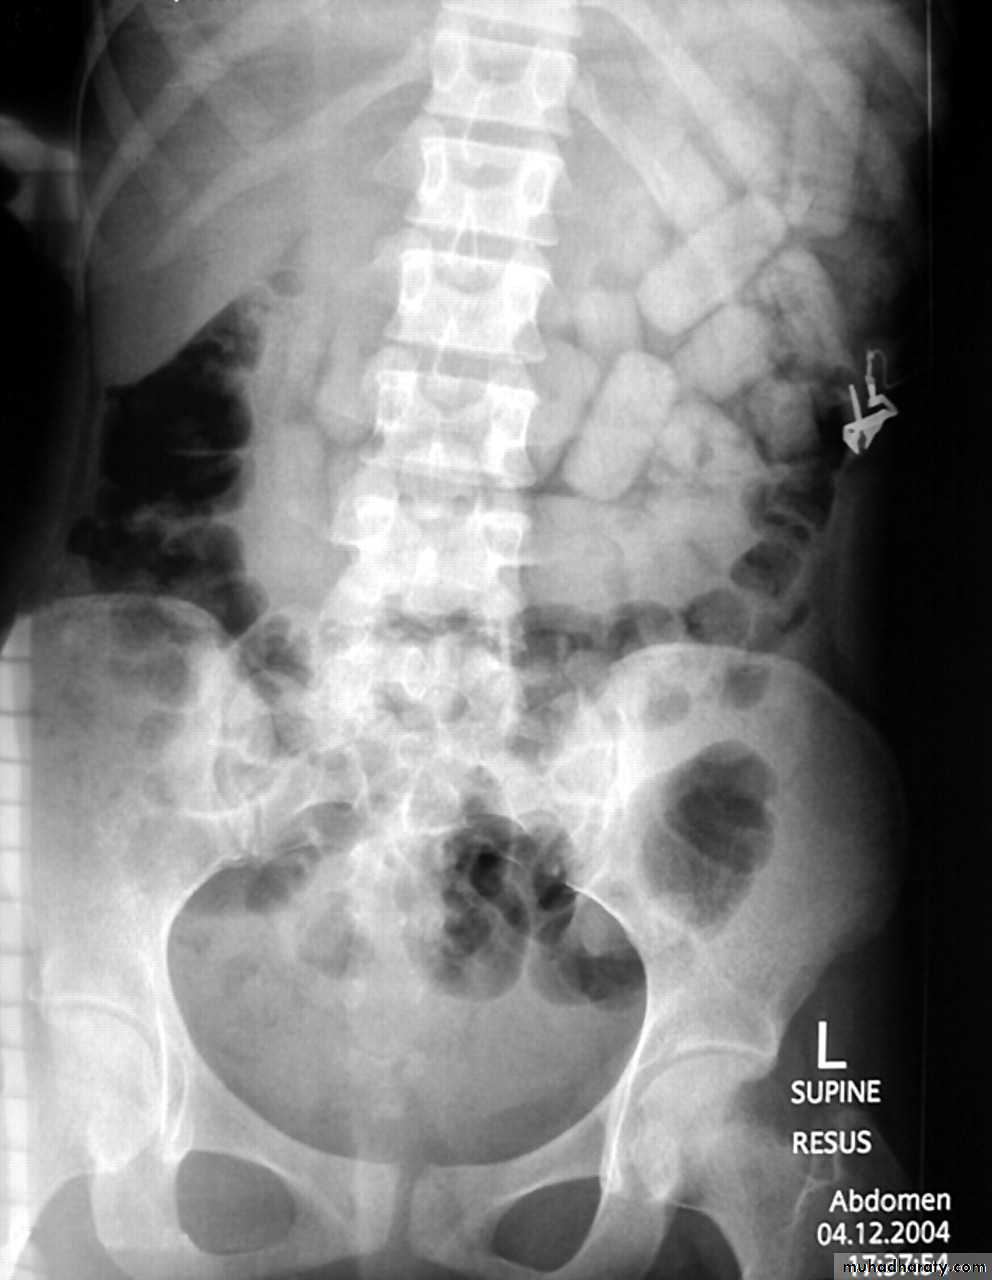

C-Radiographic examination:

-Limited role.-Lack of Radiopacity. (Undetectable by x ray).

Ferrous or Potassium salt could produce significant opacities.

Enteric coated formulations or restrained release could be opaque, Lead pica (in children)-CXR.

-Plain X ray Of the Abdomen.

-CT Scan.

Carbon tetrachloride and chloroform are radio opaque in gut lumen.

Foreign Body in GIT (Body packers)Latex plastic storage.